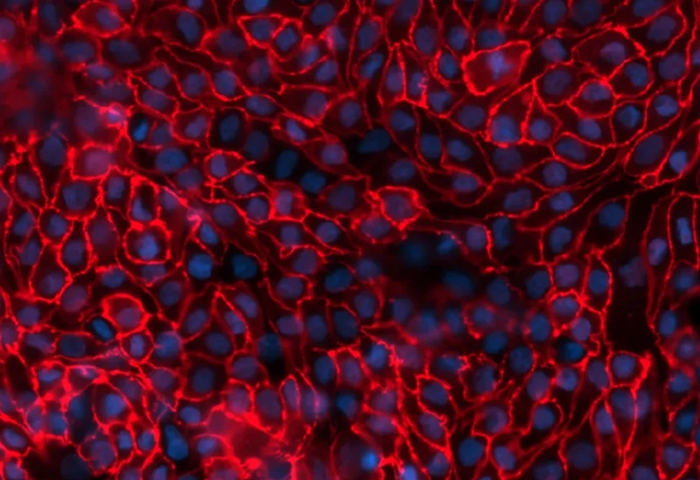

Zo-1 Immunocytochemistry staining of PTCs (red) and Hoescht nuclear staining. Image Credit: Newcells Biotech

aProximateTM is a highly advanced in vitro model of kidney PTCs that mimics physiological conditions. aProximateTM PTCs are derived from fresh human kidney tissue and grown on Transwells®. They remain well differentiated as a polarized cell layer with tight junctions.